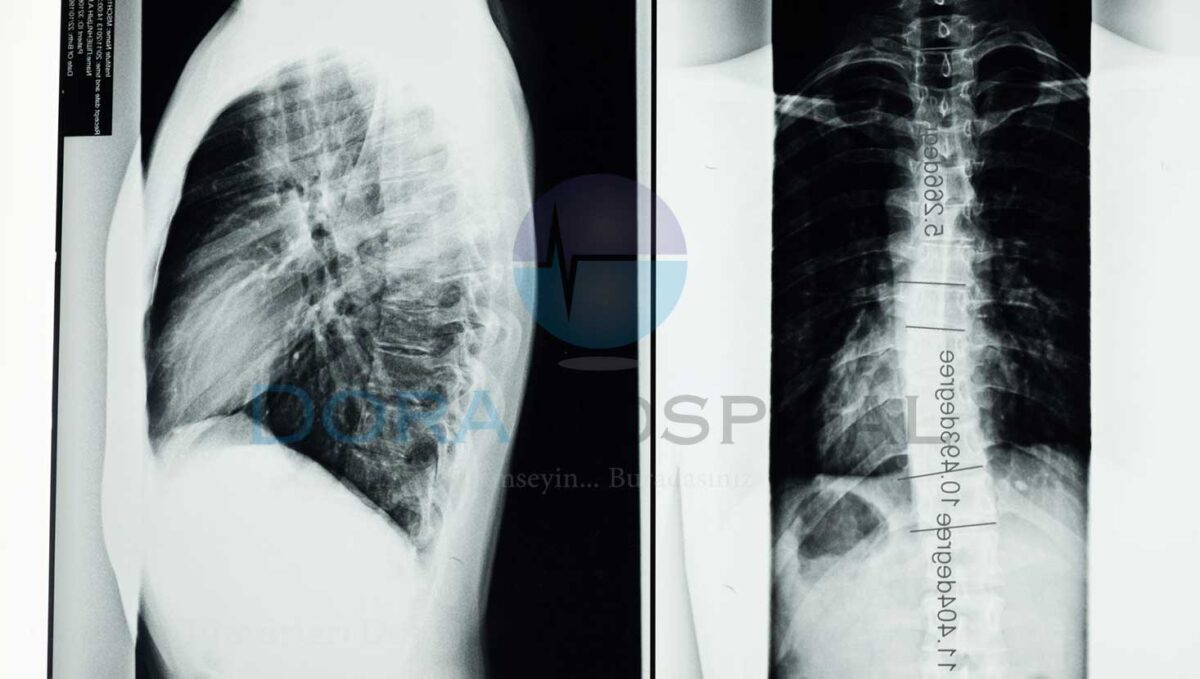

Omurga Tümörü Tanı Yöntemleri

Omurga tümörü tanı yöntemlerinde ilk olarak hastanın tıbbi öyküsü alınmaktadır. Daha öncesinde kanser geçirmiş olması veya ailesinde kanser öyküsü bulunan bir kişinin olması genellikle omurga tümörü ile karşı karşıya kalma riskini daha da yükselmektedir. Hekim hastanın aile öyküsünü de aldıktan sonra fiziksel bir muayene gerçekleştirmektedir. Fiziksel muayene sonrasında tümörden şüphelenilmesi ile birlikte MRI gibi omurilikte bulunan görüntüler alınmaktadır.

MRI haricinde bilgisayarlı tomografi de istemek mümkün olmaktadır. Yapılacak olan radyasyon ışınları ile bölgede ki tümörün net ve detaylı bir şekilde görüntülenmesi sağlanmaktadır. Belli başlı enjekte yöntemleri ile birlikte de tümörün daha net bir şekilde ortaya çıkması sağlanmaktadır. Ancak yaygın olarak tercih edilen yöntemler arasında bulunmamaktadır.

Omurga tümörü tanısında biyopsi en net tanıyı koyulmasına yardımcı olmaktadır. Alınan küçük doku örneği ile birlikte tümörün DNA yapısı, iyi huylu veya kötü huylu olup olmadığı gibi birçok sorunun cevabı rahat bir şekilde alınmaktadır. Bunun sonucunda ise hastanın durumuna göre tedavi planı hazırlanmaktadır.